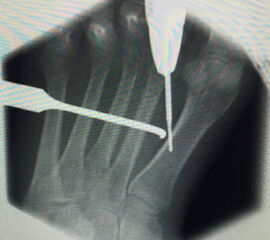

=> Risikoabwägung der radiologisch leicht erhöhten Strahlenbelastung intraoperativ

In der minimalinvasiven Fußchirurgie ist es unabdingbar, die Fräse in ihrer Position zum Knochen radiologisch zu kontrollieren, damit vulnerable Wachstumsfugen oder angrenzende Gelenke nicht verletzt werden. Zu diesem Zweck werden mit einem Bildwandler während der Operation die genaue Position der Fräse und der Osteotomieverlauf überprüft, was die Strahlenbelastung im Vergleich zu offenen Verfahren erhöht. Diese Strahlenbelastung hat potenziell einen schädigenden Einfluss auf den noch blutbildenden Knochen von Heranwachsenden. Gesicherte Landmarken am Fuß können die notwendige Zahl der Röntgenbilder und damit die Strahlung minimieren. Ist es erforderlich, mehrere Knochen zu osteotomieren, wie zum Beispiel im Bereich der Kleinzehen, werden anhand der Landmarken kleine Injektionsnadeln auf Höhe der geplanten Osteotomien vorgelegt und radiologisch im Bildwandler (BV) dokumentiert (Abb. 11). Ein solches Bild schafft eine gute Orientierung, sodass auf radiologische Kontrollen intraoperativ weitestgehend verzichtet werden kann.

Abb. 11: Lokalisation mehrerer Stichinzisionen mit einem Röntgenbild.